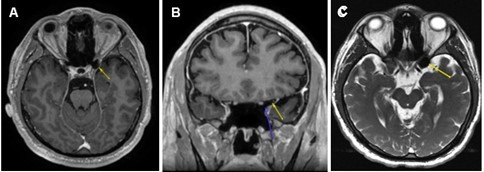

Based on the patient’s surgical history, ophthalmic exam, OCT, and 24-2 test results, brain and orbit MRI with and without contrast were ordered to identify lesions along the visual pathway, notably the optic nerve tract, chiasm, or occipital lobe. The MRI revealed no intra-orbital pathology and no abnormal enhancement of the optic nerve/chiasm/radiations or brain parenchyma. Of note, axial post-gadolinium T1-weighted MRI (Figure 1 A) demonstrated an area of hypointensity in the left ACP that measured 1.46 cm x 1.31 cm consistent with the presence of air-filled space involving about 50% of the left ACP. The coronal view of his gadolinium T1-weighted MRI (Figure 1B) clearly delineated the air-filled space with no obvious hematoma or traumatic optic nerve lesions noted. The axial T2-weighted FIESTA-C (modification of the basic FIESTA/True FISP sequence) MRI (Figure 1C) showed hypointensity in the left ACP. There was no discernible optic canal stenosis, change in optic nerve course, or optic nerve dehiscence or protrusion associated with the ACPP. The patient was referred to neurosurgery for further evaluation. His head and orbit CT scans revealed no bony fragment or hematoma affecting structures in the visual pathway. No surgical intervention was entertained, as the risks significantly outweighed any perceived benefit. At 6 months follow-up, the patient had no improvement of blurred vision in his left eye.

Figure 1.(A) Axial post-gadolinium T1-weighted MRI demonstrating the T1 hypointensity in the left anterior clinoid process (yellow arrow). (B) Coronal post gadolinium T1-weighted MRI with two arrows outlining a clearly delineated air-filled space without a hematoma or traumatic lesion to optic nerve just superior to the tip of blue arrow. (C) Axial T2-weighted FIESTA-C MRI showing T2 hypointensity in the left anterior clinoid process (yellow arrow).